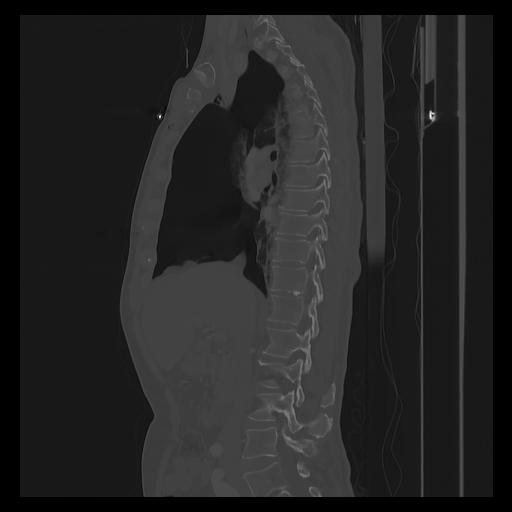

33 PULMON,CE,Sagittal,3.000,PULMON,Sagittal,